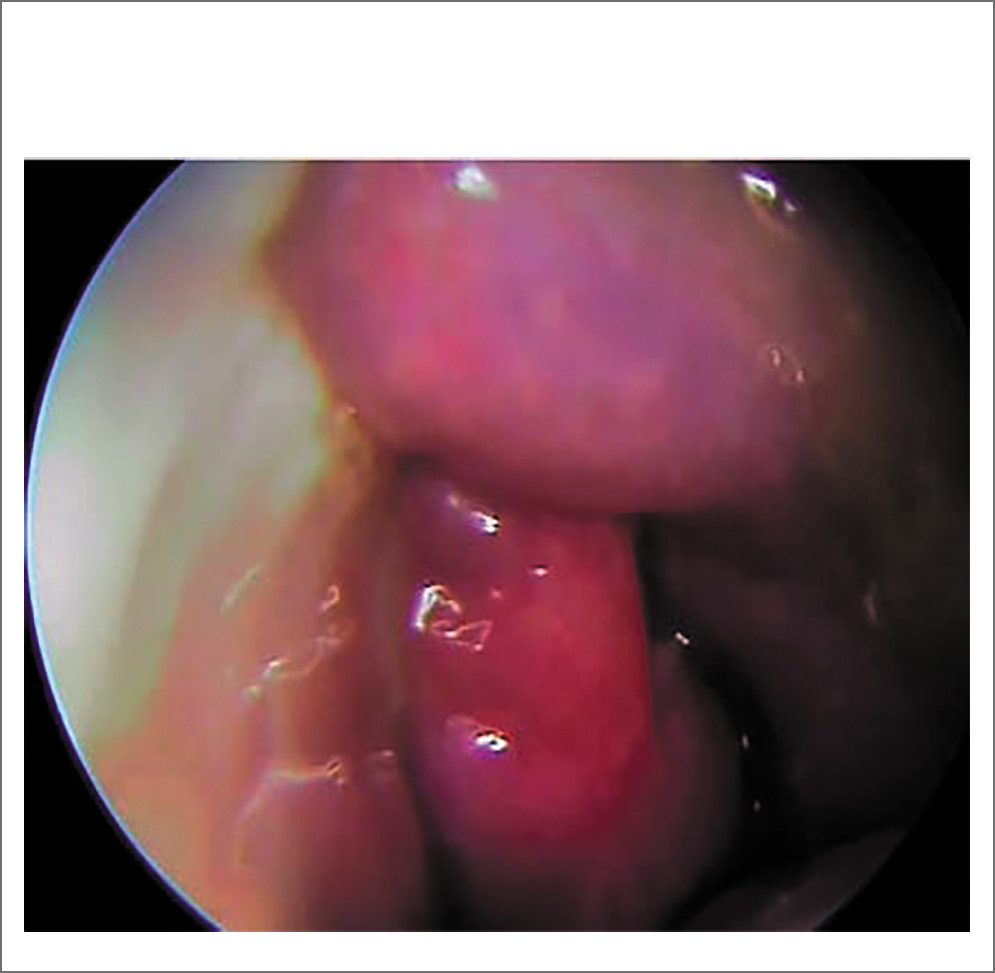

После эндоскопической визуализации полости носа и регистрации слева полипозных вегетаций с характерной окраской и консистенцией, обильным выделением густого слизистого секрета (рис. 2) и предыдущей КТ носа и ОНП пациентке выполнена МСКТ с контрастным усилением, заключение: тотальное затемнение левой гайморовой пазухи, клеток решетчатого лабиринта с разрушением медиальной стенки ВП и проникновением в полости носа, смещение носовой перегородки и компрессия средней носовой раковины, наличие группы гиперденсивных включений округлой формы, контраст не накапливается (рис. 3). После выставления диагноза левостороннего хронического ПРС, мицетомы гайморовой пазухи и проведения соответствующей предоперационной подготовки пациентке выполнена гайморотомия по Колдуэлл–Люку, этмоидотомия слева. Отмечено в левой ВП наличие органических субстратов высокой плотности. Интраоперационно взятые подозрительные фрагменты поврежденных тканей направлены на гистологическое исследование с соответствующим диагнозом (рис. 4).

Рис. 2. Назальные полипы в носовом ходе слева, густой слизисто-гнойный секрет.

Рис. 4. Удаленные фрагменты образования ВП.